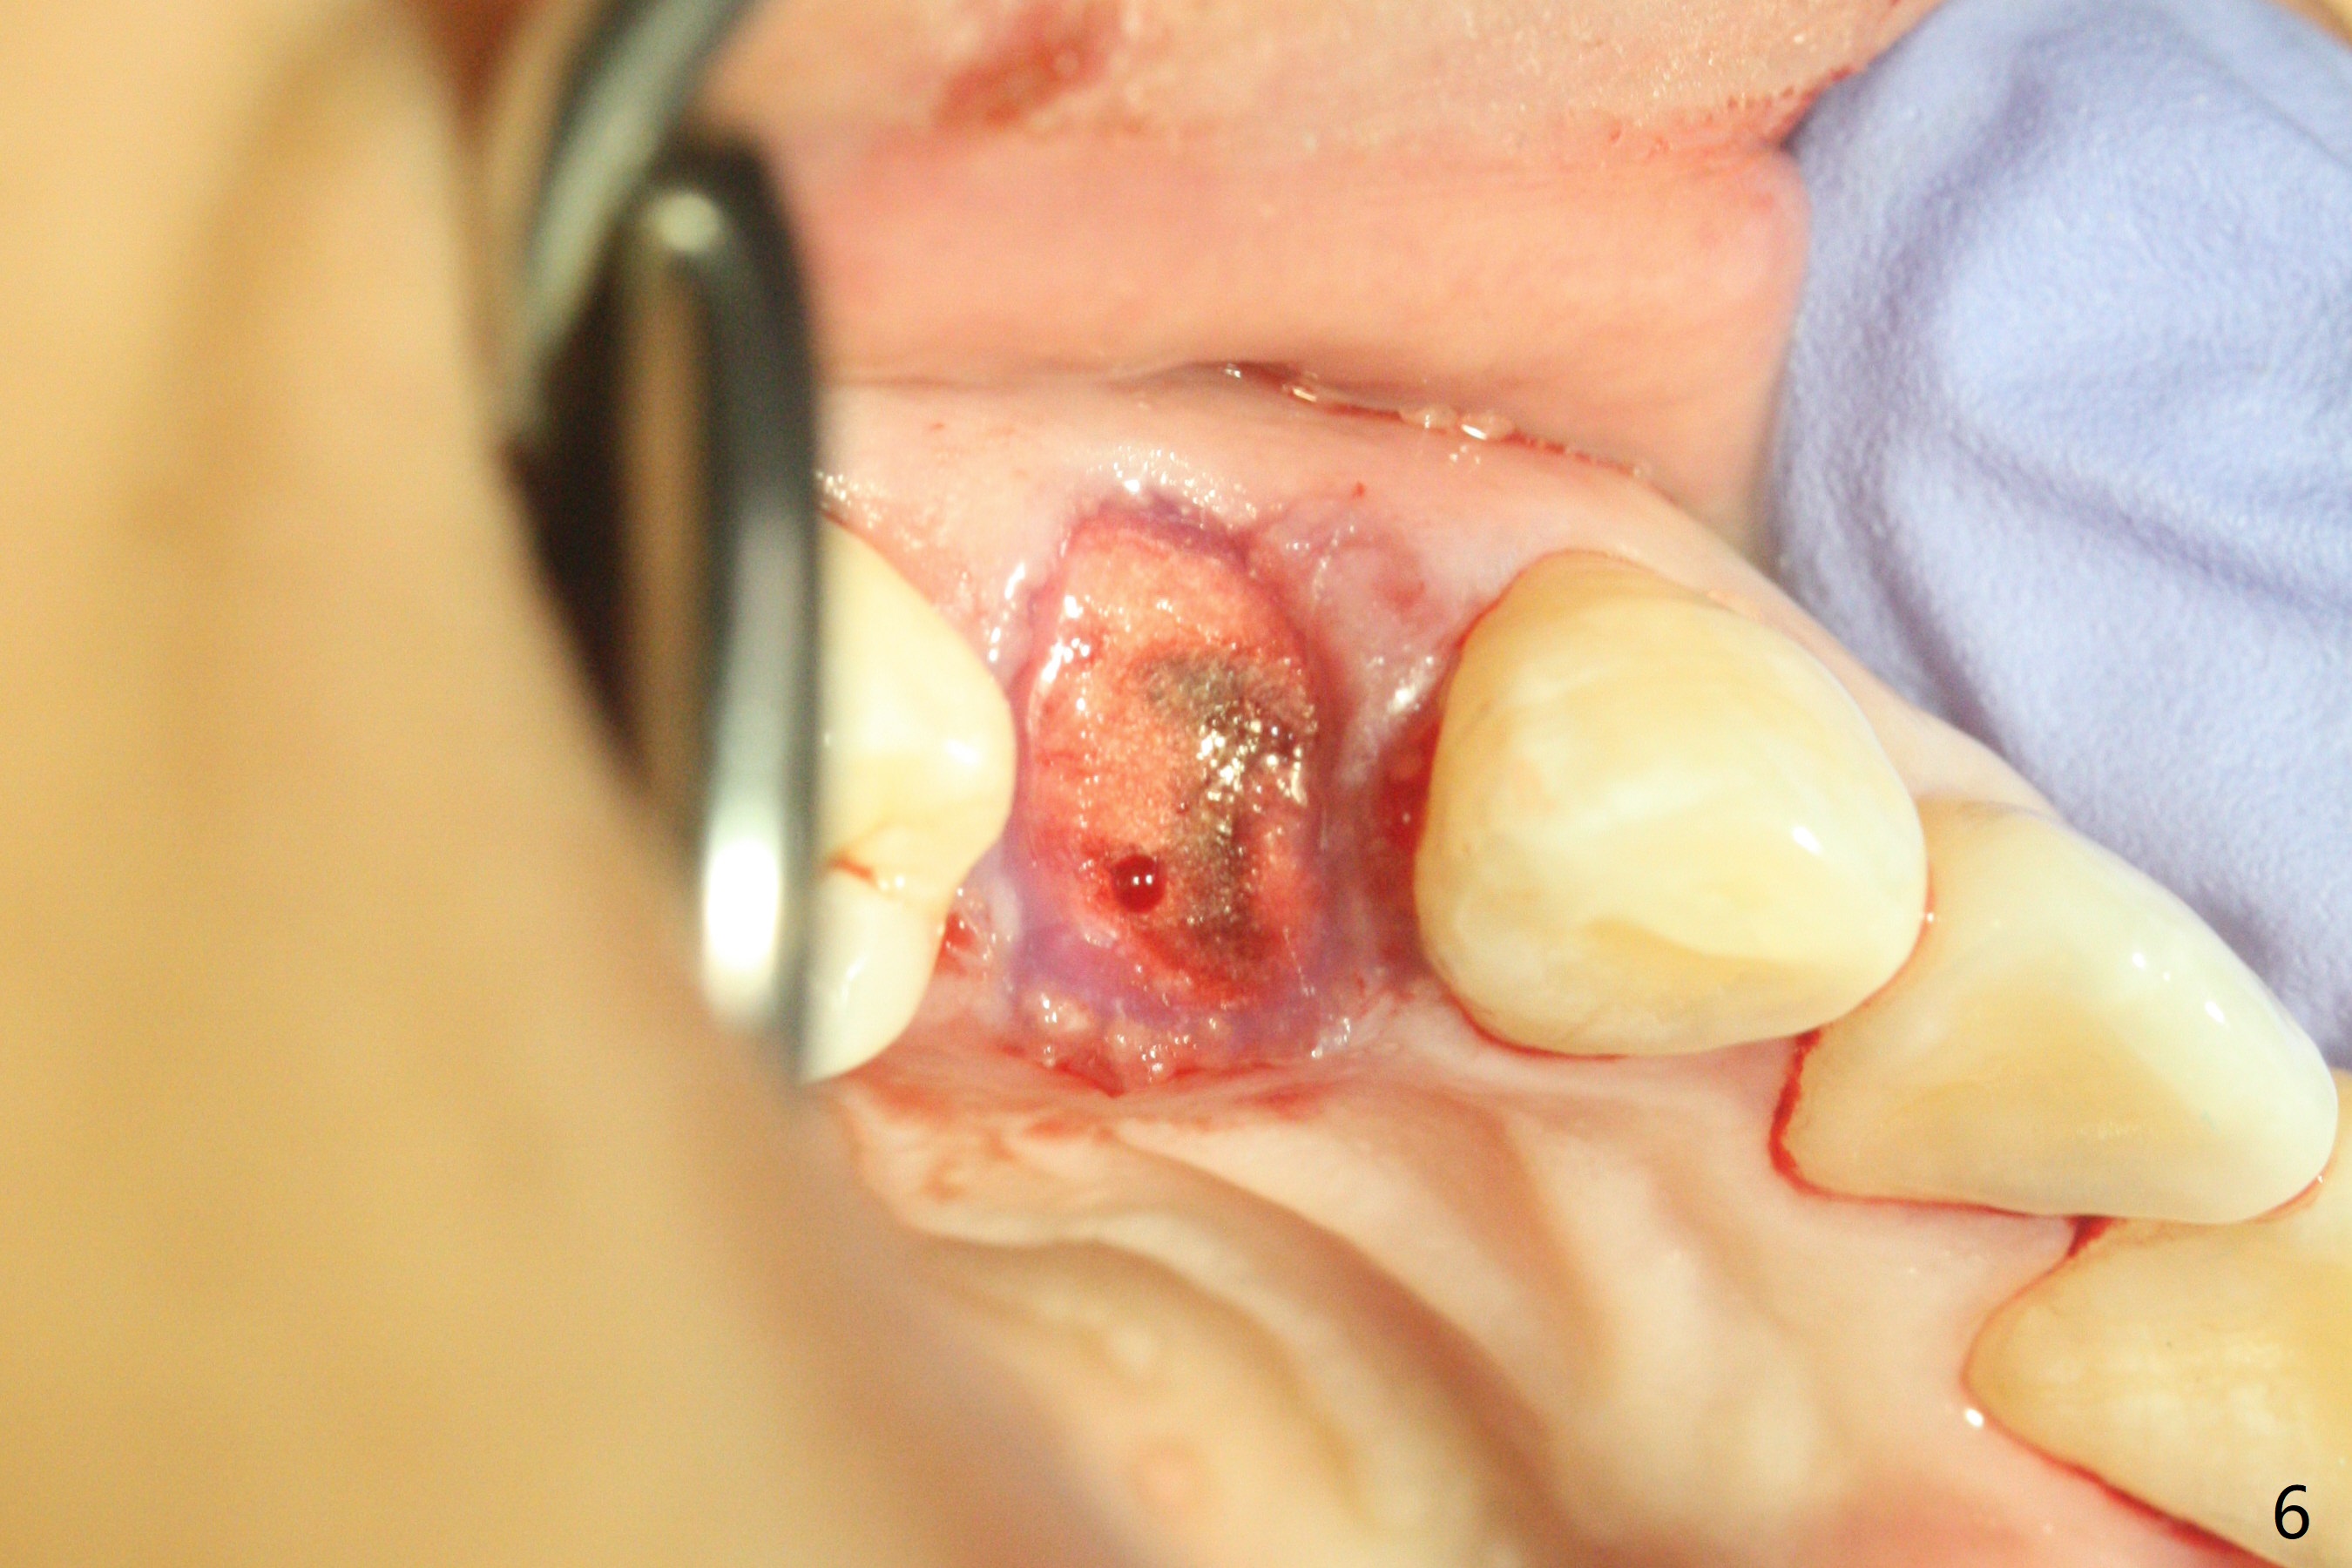

今天临床实践让我对植骨概念和操作有两方面突破,与大家分享讨论。PRF/sticky bone(粘性骨粉)以及血小板因子(成品)对软硬组织缺损修复重建无疑起到不可缺少作用。但是大多数拔牙病例并不是那么严重,放置骨粉和覆盖胶原膜足够了。为了避免费时的缝线固定胶原膜,介绍一种简易固定方法,助手可以做。31岁女不想保留严重龋坏右上4(图一至四,拍摄临床照片,与后期比较,但愿简易植骨不产生骨板塌陷),虽然术前根尖片显示根尖阴影(图四),术中没有根尖骨板缺失。估计没有严重骨板缺损,她又年轻,再生能力强,所以做简易植骨(异体骨,图五),也就是不需要PRF或者血小板因子,骨粉表面放置GEM CAP(9-12月吸收膜),由胶水固定(图六),在放置牙周敷料前,在胶原膜表面涂一层含有抗单纯疱疹病毒凡士林(图七),但愿敷料脱落时,不至于把胶原膜带下来。术后第六天,病人由于左上第二磨牙不适回来,说敷料脱落,没有不适,要求检查,其实膜也丢失(图八,九),骨粉好像挺稳定,没有做如何处理,尽管少量骨粉离开牙槽窝(<)。